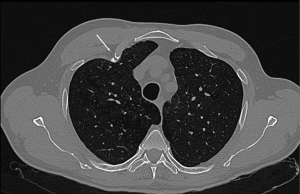

Rib fractures represent an important indicator of trauma severity; of note, morbidity and mortality increase as the number of fractured ribs increases. In one manuscript previously reported, 81% of patients with two or more rib fractures had either haemothorax or pneumothorax (8). The supine frontal radiograph is usually the initial imaging study obtained in a trauma patient, despite some authors have reported the modest sensitivity of anteroposterior (AP) chest radiograph for thoracic injuries. As a matter of fact, in this study of 374 patients with blunt trauma, approximately half of all pneumothorax, rib fractures, and pulmonary contusions were not apparent on AP chest radiograph (9). Nevertheless, some studies have shown that posteroanterior (PA) radiograph has a good specificity but not sensitivity for rib fracture, although its sensitivity is higher than those of AP radiograph (10). In fact, up to 50% of rib fractures are missed at radiography, even when images with dedicated oblique rib views are obtained. Dedicated rib views rarely provide any additional information that would change management and should be avoided (7). The American College of Radiology (ACR) has established an algorithm for the imaging evaluation of rib fractures (11). The first decision involves evaluation of the mechanism of injury. For blunt trauma with a high-energy mechanism, CT angiography or contrast-enhanced chest CT should be performed. In these situations, the examination is tailored to investigate soft-tissue, vascular, and internal organ injuries. Chest radiography is a complementary examination; injuries are underestimated on AP radiograph when compared with CT images (12). Other authors have reported the role of US in the detection of rib fractures. US is more sensitive in the detection of rib fractures including chondral rib fractures, as compared with conventional radiography (78% and 12%, respectively). Trans-thoracic US of the chest is useful in the evaluation of a wide range of peripheral, parenchymal, pleural, and chest wall diseases and missed rib fractures (13).

A nondisplaced rib fracture is defined as a rib fracture with complete cortical disruption but with maintained alignment, usually involving the medullar bone and both the inner and outer cortices (Figure 1); it is seen such a lucent line on radiographs or CT images (14). Stress rib fractures are overuse injuries that occur when there is an abnormal force on normal underlying bone. These begin with a small stress on the bone, which with repeat injury results in a microtrabecular fracture that may progress to rib fracture. These injuries are rare, although possibly underdiagnosed, and most often seen in workers who perform repetitive motions and athletes. Detection of non-displaced and stress rib fractures on radiographs is difficult, and these injuries may be seen radiographically only at follow-up imaging, after signs of healing have manifested (7). On the contrary, MRI can show immediately an area of oedema (high T2 signal) after a traumatic event. When cortical disruption and a substantial abnormality in alignment are evident, a rib fracture is classified as displaced. Displacement may be minimal or obvious. Displaced fractures may be identified on radiographs or CT images (Figure 1). Injury to the surrounding tissues and structures can occur, and several lethal complications such an aortic injury have been documented in the literature (15). A buckle fracture of the rib occurs when there is disruption of either the inner or outer cortex (Figure 2) with no observable fracture of the other cortex (16). Some researchers have reported that the term buckle is derived from engineering terminology that describes disruption of the inner or tensile side of a structure that is placed under force (7,17). Flail chest (“volet”) is a traumatic condition in which there are three or more contiguous ribs with fractures in two or more places (Figure 3). Fractures usually occur in the anterior and anterolateral portions of the middle to lower ribs (1). These fractures create a flail segment that can move paradoxically relative to the remainder of the chest during respiration in a spontaneously ventilating patient. Although imaging can show fractures, it is the clinical examination that will demonstrate paradoxical motion. Flail chest serves as a marker for significant intrathoracic injury, since more than one-half of the affected patients may have associated injuries that require surgical treatment (18).